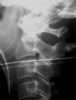

Aplasia of dens